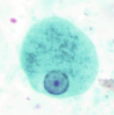

ENTAMOEBA HISTOLYTICA CYST

Professor: Dr. Glena Fe A. Yapchulay-Alcabasa